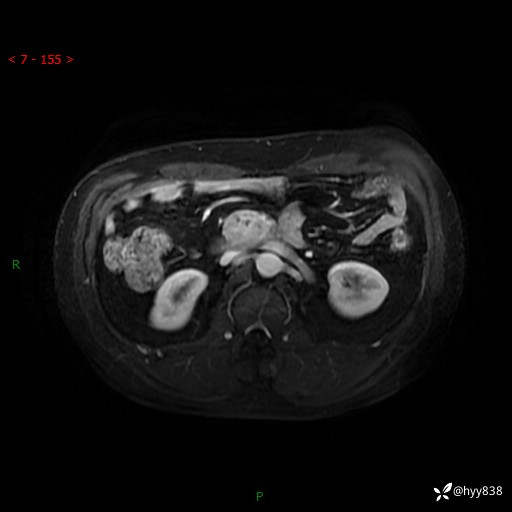

MRI(T1WI+T2WIfs+DWI)

增强